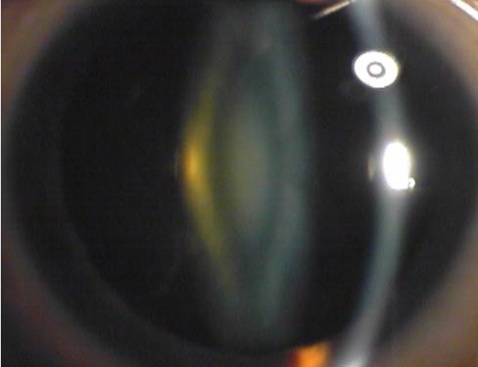

较皮质性白内障少见,发病年龄较早,进展缓慢。混浊开始于胎儿核或成人核,前者较多见,逐渐发展到成人核完全混浊。初期晶状体核呈黄色混浊,但很难与核硬化相鉴别。核硬化是生理现象,由于晶状体终身生长,晶状体核密度逐渐增加,颜色变深,透明度降低,但对视力无明显影响。对核性白内障,散瞳后用彻照法检查,在周边部环状红色反光中,中央有一盘状暗影。眼底检查仅可由周边部看清眼底。由于屈光力增加,可发生近视。远视力的减退较慢。由于中央和周边部屈光力不同,形成晶状体双焦距,可产生单眼复视或多视。因周边部屈光力没有改变,扩瞳前后的视力是不同的。核性白内障以后逐渐变为棕黄色或棕黑色。此时视力极度减退,眼底已不能看清。这种核改变可持续很久而不变,可同时有皮质混浊,但不易成熟。